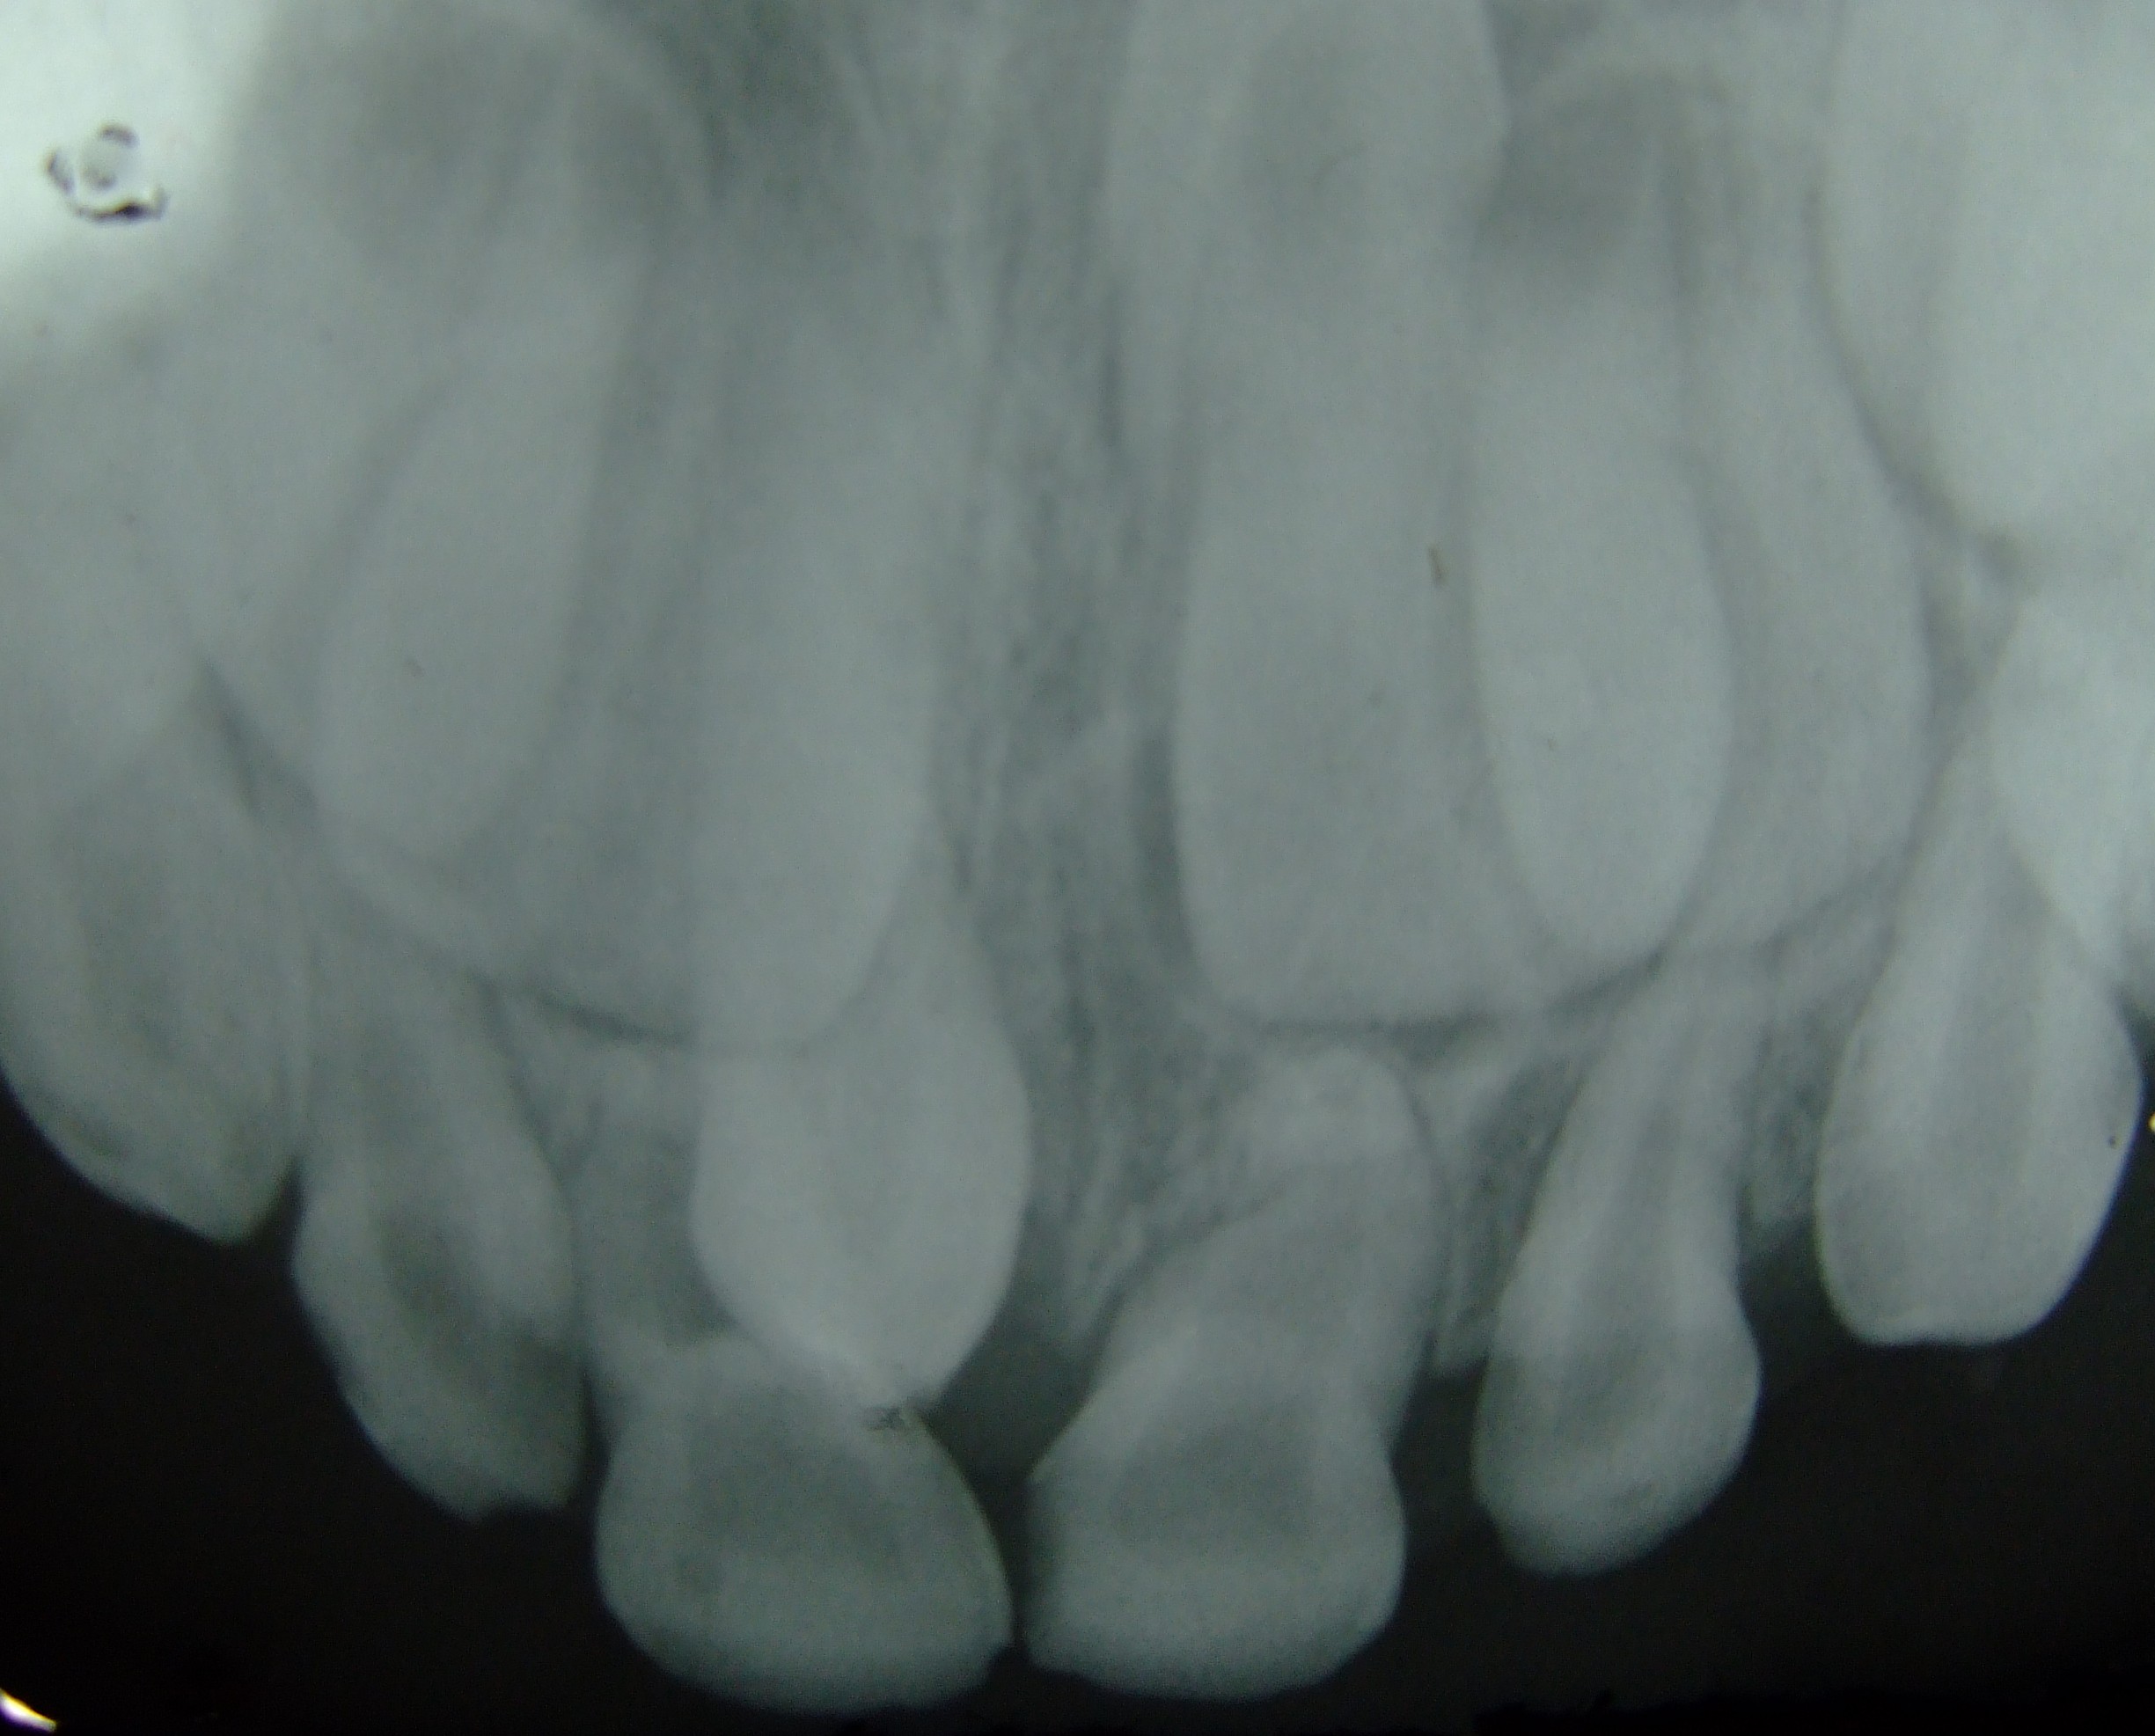

과잉치는 정상적인 치아보다 더 많은 치아가 발생하는 치과 질환이다. 유전적 요인과 환경적 요인이 복합적으로 작용하여 발생하며, 맹출 지연, 부정교합, 낭종 형성 등 다양한 문제를 일으킬 수 있다. 과잉치는 모양과 위치에 따라 여러 유형으로 분류되며, 정중 과잉치가 가장 흔하게 나타난다. 진단은 치과 X-ray를 통해 이루어지며, 치료는 수술적 제거가 유일한 방법이다. 역사적으로 과잉치는 특정 인물이나 신화, 민담, 문학 작품 등에서 언급되기도 하였다.

6. 진단

과잉치는 서로 다른 각도에서 두 개의 치과 X-ray를 촬영하여 감지할 수 있다. 구강 내 X-ray(구강 내에서 촬영하는 X-ray)와 파노라마 방사선 사진이 그 예이다. 그러나 이러한 X-ray는 2D이므로 치아의 3D 모습을 정확하게 나타내지 않는다.[2]